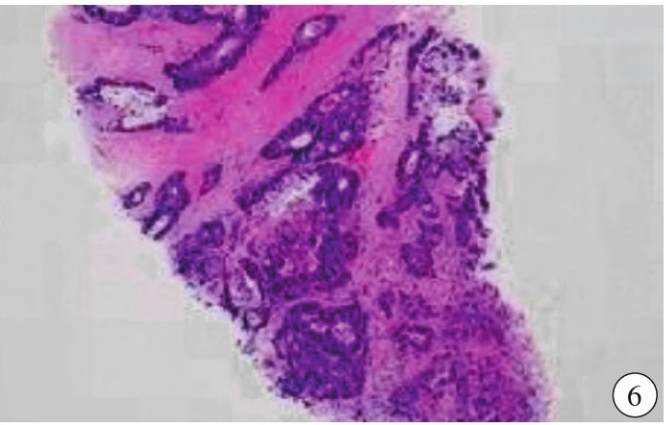

超声引导下右乳腺结节穿刺病理所见肿瘤细胞呈巢状,大小不一,于乳腺间质内生长,未侵及乳腺导管上皮,局部间质黏液变,肿瘤细胞核深染,核浆比增高,胞质淡染(图6)。免疫组织化学:Villin (+),CDX-2 (+),SATB-2 (+),MSH-2(+),MSH-6 (+),MLH-1 (+),PMS-2 (+),Her-2(3+),P120(膜+),E-cad (+),Ki-67 (Li:60%),ER (-),PR (-),GATA-3 (-),SOX-10 (-),CK5/6(-)。

图6 光镜下见肿瘤细胞呈巢状,大小不一,于乳腺间质内生长,未侵及乳腺导管上皮,局部间质黏液变,肿瘤细胞核深染,核浆比增高,胞质淡染,符合转移性腺癌(肠道来源)。